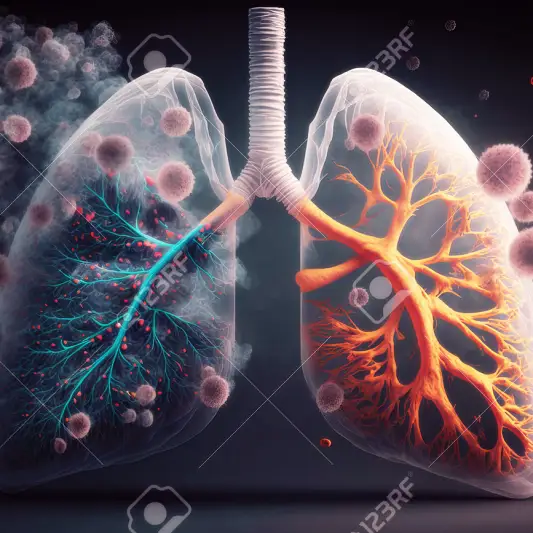

활동 수준 조절 및 운동

활동 수준 조절 및 운동은 폐암 수술후 필요한 중요한 관리 사항입니다. 수술 후 적절한 활동 수준을 유지하고 자주 활동하는 것이 중요합니다. 하지만 너무 과도한 운동은 피해야 합니다. 적절한 신체 활동은 회복을 촉진시키고 폐 기능을 향상시키는 데 도움이 됩니다.

폐암 수술을 한 환자는 수술 이후에 약간의 휴식이 필요할 수 있습니다. 그러나 지나친 휴식은 근력 감소와 폐 기능을 악화시킬 수 있습니다. 따라서 적절한 운동이 중요합니다. 폐 기능을 향상시키기 위해 걷기나 자전거 타기와 같은 유산소 운동을 꾸준히 실시하는 것이 좋습니다.

활동 수준 조절은 폐암 수술후 정말 중요한 부분입니다. 꾸준한 운동과 적절한 휴식을 통해 회복을 도모하고 건강을 유지할 수 있습니다. 폐암 수술후 관리와 후송 기간동안 이러한 사항들에 유의하여 좋은 결과를 얻을 수 있기를 바랍니다.